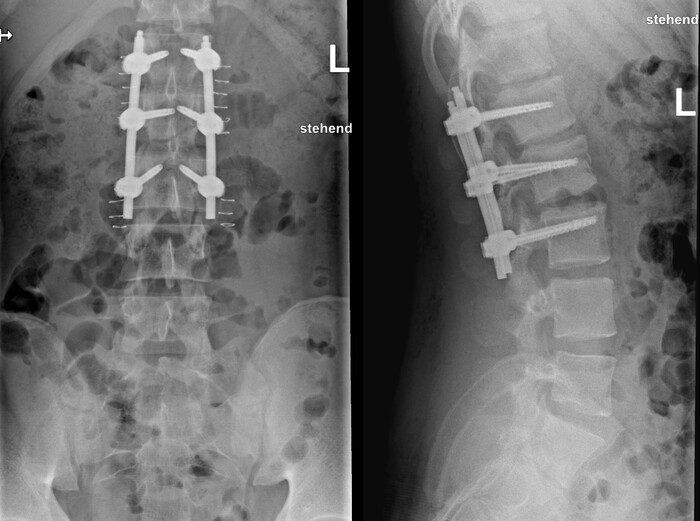

Сделали компьютерную томографию почти всего тела по протоколу множественной травмы (голова, шея, органы грудной клетки + органы брюшной полости включая позвоночник и таз).